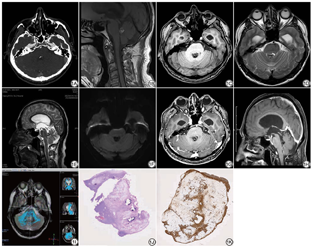

患者男,59岁,自诉于一周前无明显诱因出现头晕、头痛,呈间断性胀痛,头昏沉感,头晕时感天旋地转,同时伴黑蒙,偶感恶心,无明显呕吐,坐立时头晕能缓解,1天前再次出现头晕表现,随后摔倒,于2022年3月7日来我院就诊。专科检查:患者神志清,精神不佳,语言缓慢,理解能力正常,双侧瞳孔等大。实验室检查:大生化γ球蛋白19%,A/G 1.22。既往史:慢性胃炎、食管炎病史,口服奥美拉唑胶囊。头颅CT血管造影(CT angiography, CTA)检查示第四脑室内可见多个点状钙化影(图1A)。头颅MRI检查示第四脑室可见一结节样异常信号,大小约11 mm×8 mm,边界清楚,形态欠规整,与小脑蚓部及脑干关系密切,T1WI呈高信号,其内可见斑点状低信号(图1B),T1WI压脂呈等低信号(图1C),T2WI呈高低混杂信号,周围可见脑脊液环绕(图1D~1E),扩散加权成像(diffusion-weighted imaging, DWI)呈低信号(图1F),双侧侧脑室、第三脑室扩大,增强扫描后第四脑室病变强化不明显(图1G~1H),波谱成像病变区Cho峰、NAA峰未见明显升高,纤维束成像第四脑室内未见纤维束走形(图1I),周围纤维束环绕,未见中断及推移。MRI诊断为第四脑室占位性病变并梗阻性脑积水,考虑:室管膜瘤、脑膜瘤。手术记录:2022年3月17日在我院行第四脑室占位切除术,术中见第四脑室内11 mm×8 mm大小的肿瘤组织,质地硬,包膜完整,内有钙化,与小脑蚓部及脑干关系密切,完整切除肿瘤组织。组织病理检查:肿瘤组织由纤维脂肪及少量短梭形及类圆形的细胞组成,间质有钙化,罗氏染液做免疫组化协诊(图1J)。结合免疫组化结果,病变符合小脑脂肪神经细胞瘤。免疫组化:NeuN(+)、Olig-2(散在+)、GFAP(+)、EMA(-)、PR(-)、CD34(-)、STAT6(-)、Ki-67阳性率约1%(图1K)。

结合本例影像表现,病变发生在第四脑室,与小脑蚓部及脑干关系密切,是较为罕见的发病部位,结合头颅CTA可见有点状钙化密度,符合小脑脂肪神经细胞瘤间质内有钙化的特点。T1WI呈高信号,其内可见低信号,脂肪抑制T1WI像可见信号减低,T2WI呈高度混杂信号,表明病变内有脂肪组织成分。DWI呈低信号。病变边界清楚,并引起梗阻性脑积水,使双侧的侧脑室及第三脑室扩大,无明显瘤周水肿。进行增强后病变无显著强化,与脂肪组织不强化的特点相符。患者为中年男性,考虑到发病年龄、性别及影像特点,需要与以下肿瘤鉴别:(1)少突胶质细胞瘤,好发于成人,高峰发病年龄为50~60岁,儿童鲜见,男性略多于女性;易侵犯大脑皮质和大脑半球,尤以额叶多见,约占60%,小脑、脑干、脊髓等部位亦可受累;影像学表现多为低或等密度影,边界清楚,常见钙化;少突胶质细胞瘤中无脂肪瘤样成分[9]。(2)中枢神经细胞瘤,中青年人群中较为多见,常位于侧脑室或第三脑室,尤其是近中线区域的透明隔或室间孔旁,T1WI呈等信号,T2WI呈等信号,囊变、钙化及血管流空影较为多见,典型的囊变可以在T2WI像表现为皂泡样的改变,增强呈不均匀强化[10]。